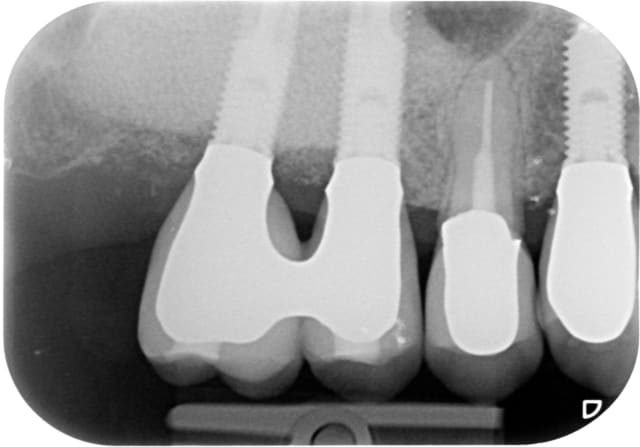

la suite...

G 21 janvier 2011 xurlrw - Eugenol

H 19 fevrier 2013 tvy4db - Eugenol

I  21 janvier 2014 gyys5o - Eugenol

J 21 mai 2014 i8zdgv - Eugenol

Jj 16 octobre 2014 clat7g - Eugenol

Jjj 16 otobre 2014 yevkyg - Eugenol